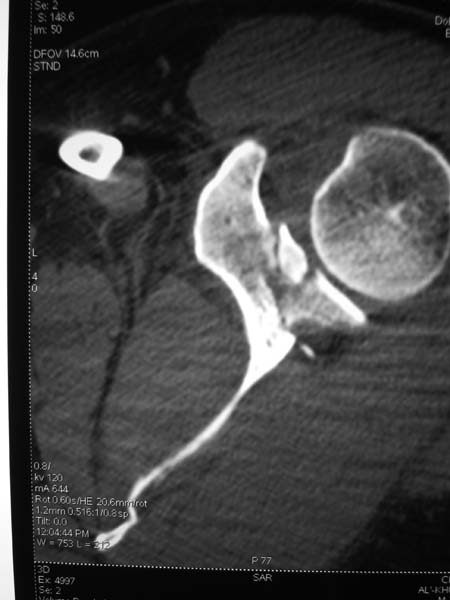

КТ отправляю

Я бы оставил все как есть. ориентация гленоида нормальная, перелом суставной поверхности без существенного смещения

Латеральный край лопатки развернут в антеверсию вместе с суставной впадиной лопатки, плюс суставная впадина при этом мигрировала медиально. В таком случае считаю важным развернуть латеральную "колонну" обратно путем остеосинтеза тела лопатки. Внутрисуставные фрагменты пока загадка. Сами по себе они могут особо не мешать, но там может быть тяжелый SLAP.